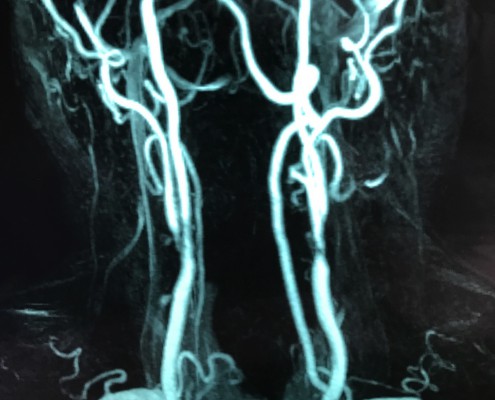

Frauen haben schlimmere Schlaganfälle/Vorhofflimmern

C. Diehm

Ein Register der österreichischen Schlaganfallkliniken…